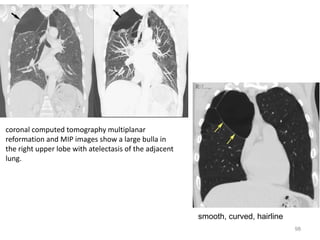

coronal computed tomography multiplanar

reformation and MIP images show a large bulla in

smooth, curved, hairline